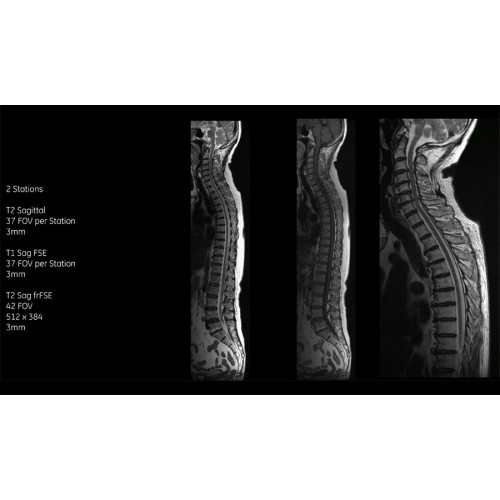

• Технология Digital Surround Technology (DST) — это новая технология объемной оцифровки данных, объединяющая сигналы от каждого элемента катушки. Прекрасное соотношение сигнал/шум и чувствительность поверхностных катушек в сочетании с превосходной однородностью и высокой проникающей способностью встроенной радиочастотной катушки — все это позволяет создавать качественные изображения не только позвоночника, но и всего тела.